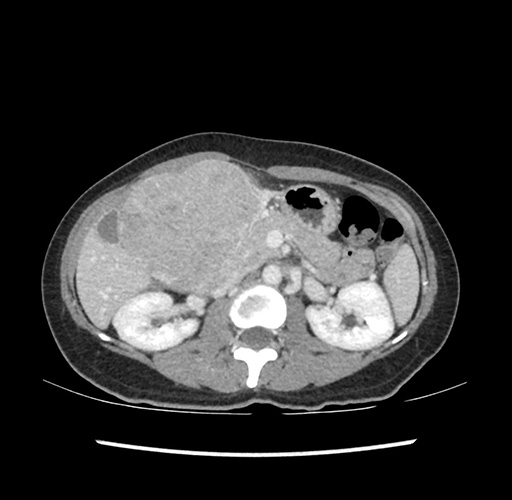

Imaging Analysis

Look through the patient's CT scan to identify any areas of concern for the necessary procedure.

Based on your CT findings, which issue(s) would give reason for "planned slowing down moment(s)" in this case?

Considering a standard left lateral sectionectomy procedure, what step(s) of the operation would you do differently in this case ?